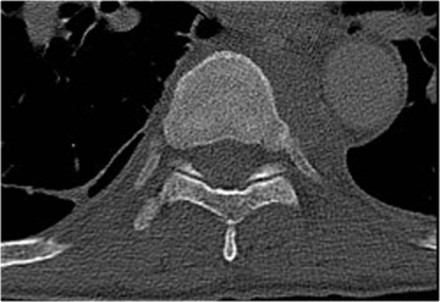

In this case of translation there is bilateral facet dislocation and also a horizontal fracture of the spinous process.

There is severe narrowing of the spinal canal.

Continue with the MRI-images.

Again look at the first MR-images and decide what is going on.

Then scroll to the next images.

The findings are:

- Anterior displacement of C7 to Th1.

- Protrusion of the disc.

- Compression of the spinal cord.

- Bone marrow edema in several vertebral bodies, either due to contusion or fracture.

- Interspinous edema and disruption of the ligamenta flava C7-Th1 and supraspinous ligament Th1-Th2.